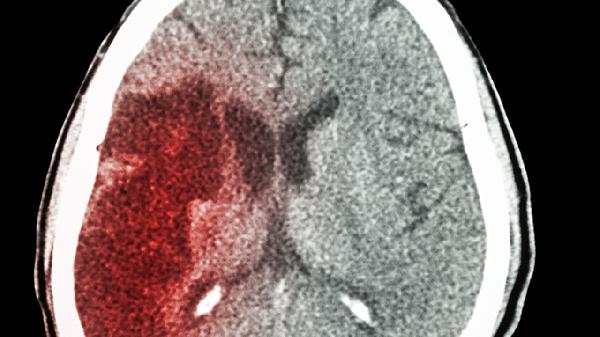

脑灵片含有多种改善脑血管微循环的成分,能增加脑部血流量,为脑细胞提供充足氧气和营养。该作用有助于缓解因脑供血不足导致的头晕头痛症状,对脑血管功能紊乱引起的记忆力减退有一定改善作用。遵医嘱使用脑灵片可辅助治疗脑血管功能障碍。